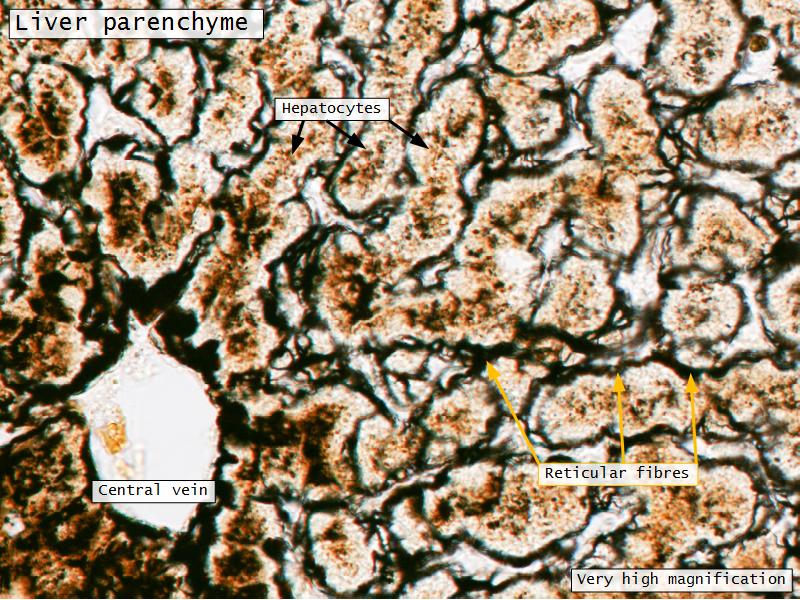

Portal vein vs Central vein

The portal vein is part of the portal triad. It has an associated artery and bile duct. The central vein has no other structures around it, and the endothelium is indistinct. You can most the times also see the sinusoids opening up into the central vein.